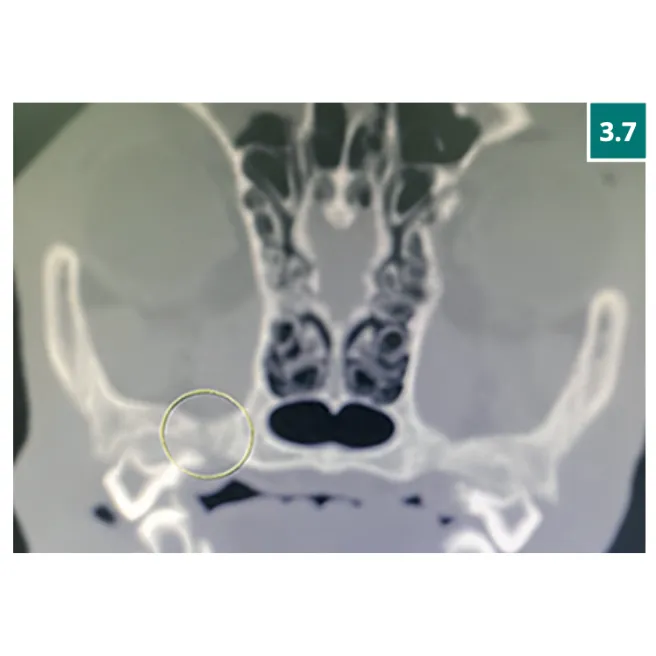

การตรวจเอกซเรย์คอมพิวเตอร์ (CT Scan) ของกะโหลกศีรษะ พบความผิดปกติหลายประการ ได้แก่

• กระดูกกะโหลกแตกหลายตำแหน่ง

• ภาวะสมองบวม (Brain edema)

• เลือดออกบริเวณสมองส่วน midbrain

• การหลุดของข้อต่อขากรรไกร (Temporomandibular Joint; TMJ) ด้านขวา